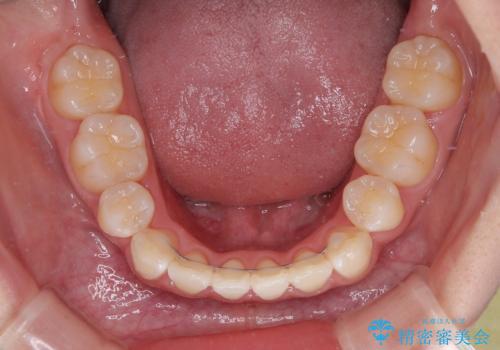

わずか2年弱で一気に口元が変化し、患者様には大変満足していただけました。